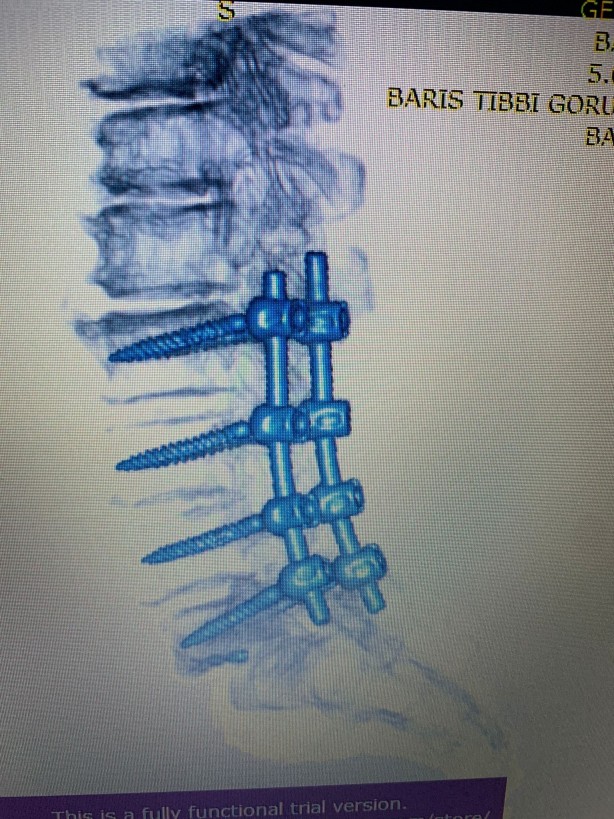

Hekimler; kırıklar, skolyoz eğrilikleri, tümörler, kanal daralması gibi ameliyatlarında vidalarla omurları desteklemede bulunuyor. Ancak vidaların bulunduğu omurlar düşme, çarpma gibi kazalar nedeniyle kırılabiliyor. Bu duruma müdahale etmek için ise açık ameliyat gerekiyor

Beyin ve Sinir Cerrahisi Uzmanı Prof. Dr. Kemal Yücesoy, vidalı omurganın kırığına dünyada ilk kez transforaminal transdiskal yaklaşımla sement desteği yaptı. Geliştirdiği yöntem, nöroşirürji alanında dünyanın en prestijli dergilerinden olan World Neurosurgery'nin son sayısında yayımlanarak literatüre girdi. Hastaların sadece 5 dakikasını alan ve 2 saat sonra günlük hayatına dönmesini sağlayan yöntem, Türkiye’ye gurur yaşattı.

Uzun süre, vidayı çıkarmadan kemik çimentosunu koyma konusunda çalışmalar yaptığını belirten Prof. Dr. Yücesoy, “Kapalı bel fıtığı ameliyatlarında iğneyle sinirin altına girerek izlediğimiz bir yol var. ‘Hastaların kemiğinin içine bu yoldan girilebilir’ diye düşündüm ve bunu da uygulamaya başladım. Bu yöntemde, hastaya lokal anestezi uyguluyoruz. Kıkırdağın olduğu bölümden diskin içine iğneyle girip oradan da kemiğin içine ulaşıyoruz ve çimentoyu koyuyoruz. Bu daha önce hiç uygulanmamış bir yol. Kırılmış vidalı bir kemiğe ilk kez o vidayı çıkarmadan kapalı yöntemle girip müdahale etmiş olduk” diye konuştu.